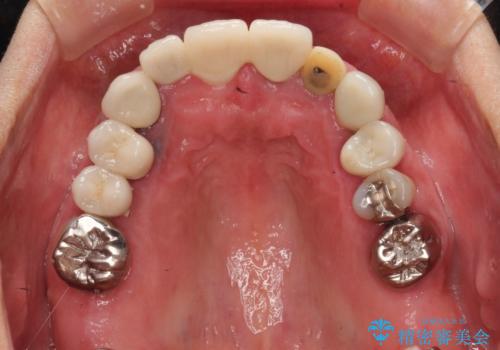

- 治療途中で装着していた仮歯汚れてしまい、恥ずかしいとのことで来院された患者様です。

土台の金属色が透けて見えてしまうため、ファイバーコアに置き換えた上で、オールセラミッククラウンにて補綴することとしました。